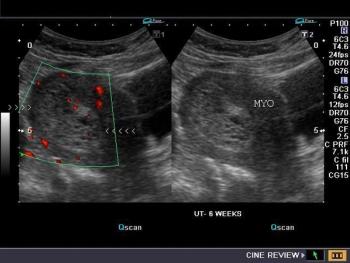

This is an early first trimester pregnancy with pelvic discomfort. What are your findings and what is a possible diagnosis?